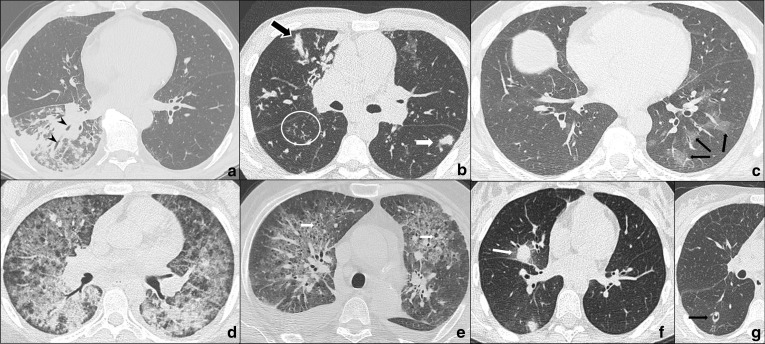

Fig. 1.

a–g COVID-19 pneumonia phases. HRTCs of patients showing the different phases and possible evolutions of COVID-19 pneumonia. In a, two subpleural, sharply demarked ground-glass opacities (white arrows in a) indicate phase 1. There is evidence of concomitant widening of peripheral vessels (black arrow in a). In b and c, subpleural extensive areas of ground glass (white arrow in c) and crazy paving pattern (black bordered white arrows in b, c) are referable to phase 2. Black arrows in b indicate dilatated segmental and subsegmental vessels. Phase 2 may also be characterised by extensive areas of crazy paving (black bordered white arrow in d), in which small consolidative foci are evident (black circle in d); In e, dependent and non-dependent consolidations (black circles in e) are hallmarks of phase 3. Phase 4 (f) presents as irregular consolidative foci (black circle in f) coexisting with confluent ground-glass opacities (white arrow in f) and crazy paving pattern (black bordered white arrow in f), whereas ARDS, which represents a possible complication COVID-19 pneumonia, is characterised by dependent consolidations (black asterisk in g) and widespread ground-glass attenuation